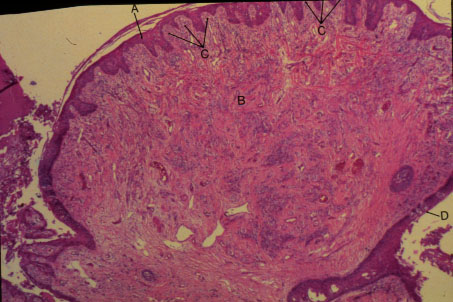

K-slide 48: Higher magnification of circumvallate papilla

A. Keratinized stratified squamous epithelium

B. [Primary connective tissue papilla]

C. [Secondary connective tissue papilla]

D. Taste bud